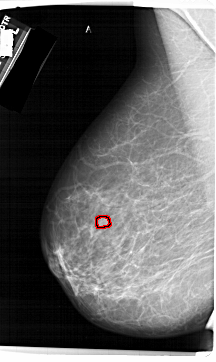

FILE: A_1423_1.LEFT_MLO.OVERLAY

TOTAL_ABNORMALITIES 1

ABNORMALITY 1

LESION_TYPE MASS SHAPE LOBULATED MARGINS CIRCUMSCRIBED

ASSESSMENT 4

SUBTLETY 3

PATHOLOGY BENIGN

TOTAL_OUTLINES 1

BOUNDARY